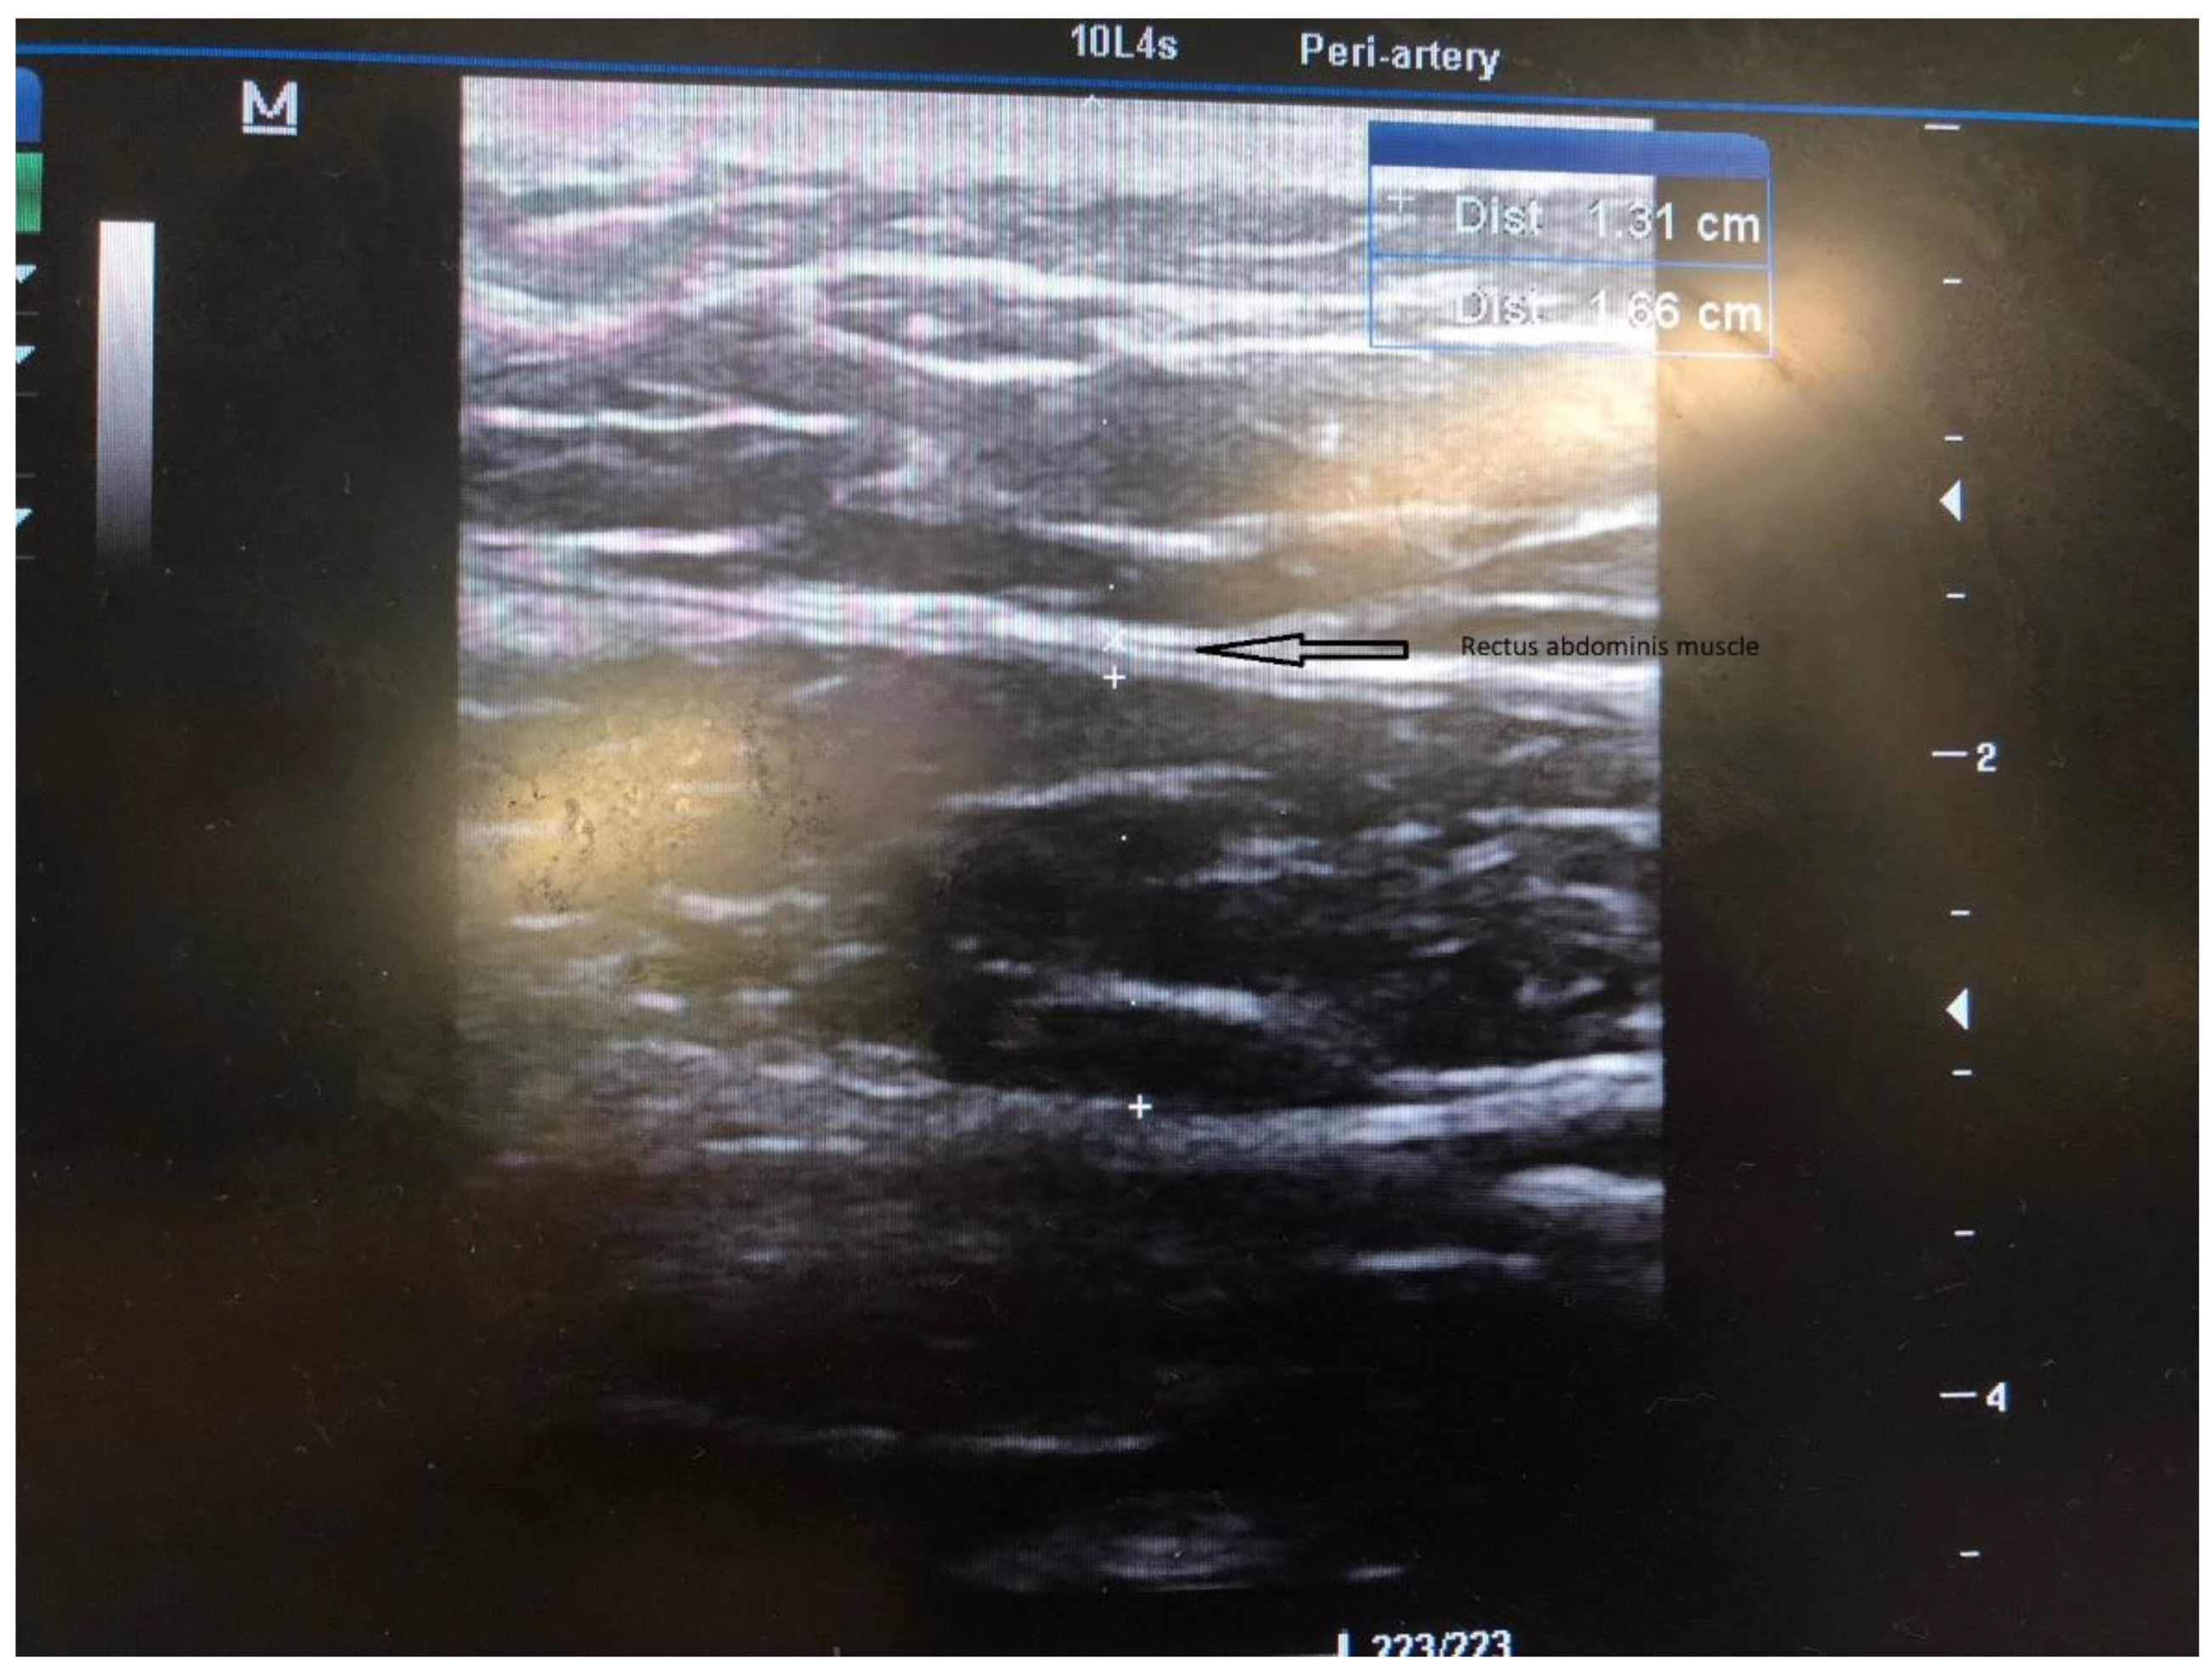

Figure 2.

US evaluation and measurement of the rectus abdominis muscle.